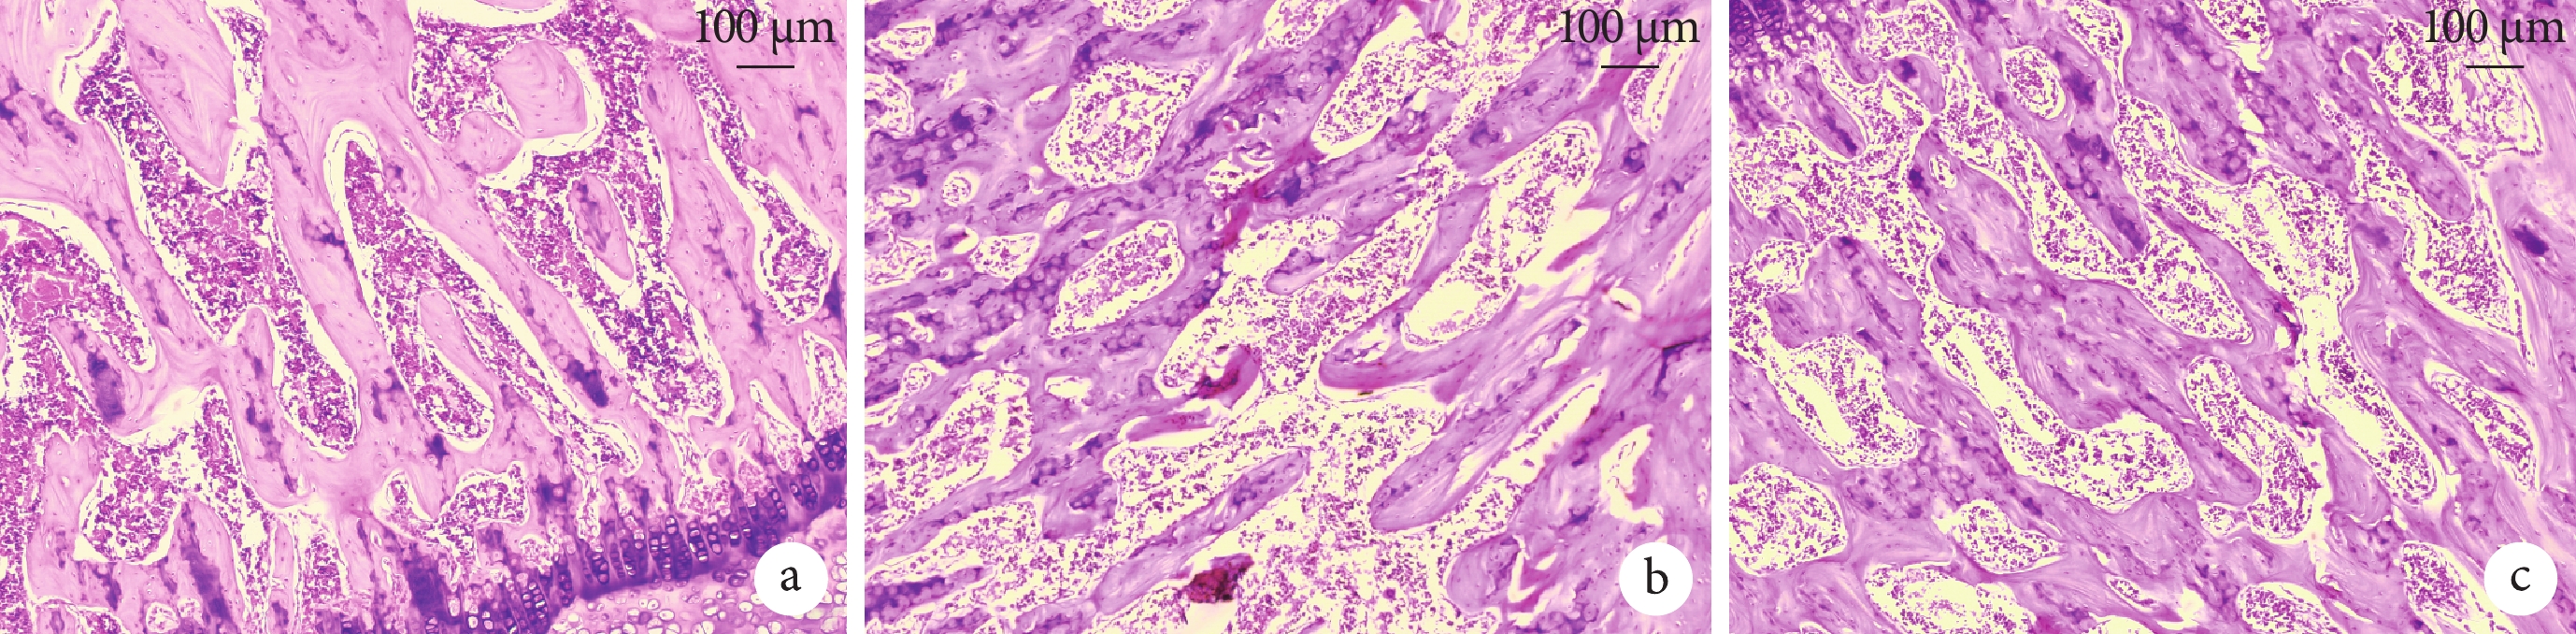

與正常對照組比較,模型組觀察到明顯骨壞死現象,表現為骨小梁結構紊亂,骨小梁周圍存在許多成纖維細胞,空骨陷窩增多,骨髓腔內充滿大量脂肪空泡,髓質造血細胞退化或壞死明顯。而干預組骨壞死程度較輕微,骨小梁雖然有僵化稀疏表現,但結構較完整,空骨陷窩形成較少,髓腔內脂肪空泡較少,造血系細胞輕度退化或壞死,但仍未達到正常對照組水平。見圖 10。

a. 正常對照組;b. 模型組;c. 干預組

Figure10. HE staining to observe the histomorphology of the femoral head in each group of rats (×100)a. Normal control group; b. Model group; c. Intervention group